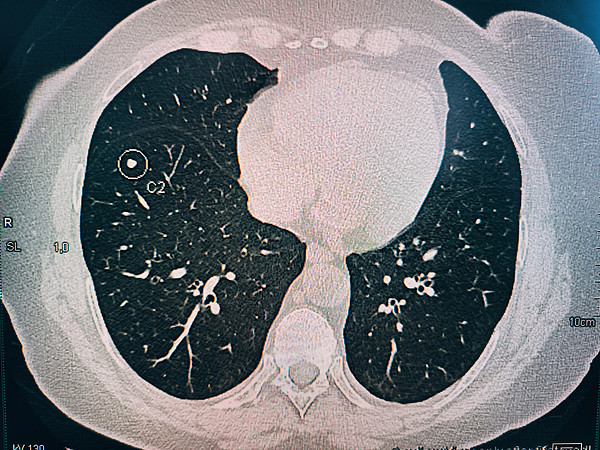

IMG_20250321_165010photo_1_2025-04-01_13-54-40photo_2_2025-04-01_13-54-40photo_3_2025-04-01_13-54-40photo_4_2025-04-01_13-54-40> > >

IMG_20250321_165010.